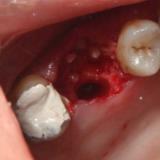

Immediate Implant Placement

A molar either maxillary or mandible always represents a little difficult and tricky scenario for implant placement immediately after extarction. There is always some sacrifice for the location, angle etc. however you save some time and patients go through a procedure once and it is a reliable method of replacing a tooth, when feasible. Dental implant is always a compromised replacement and a tooth restored with immediate placement is not any different.